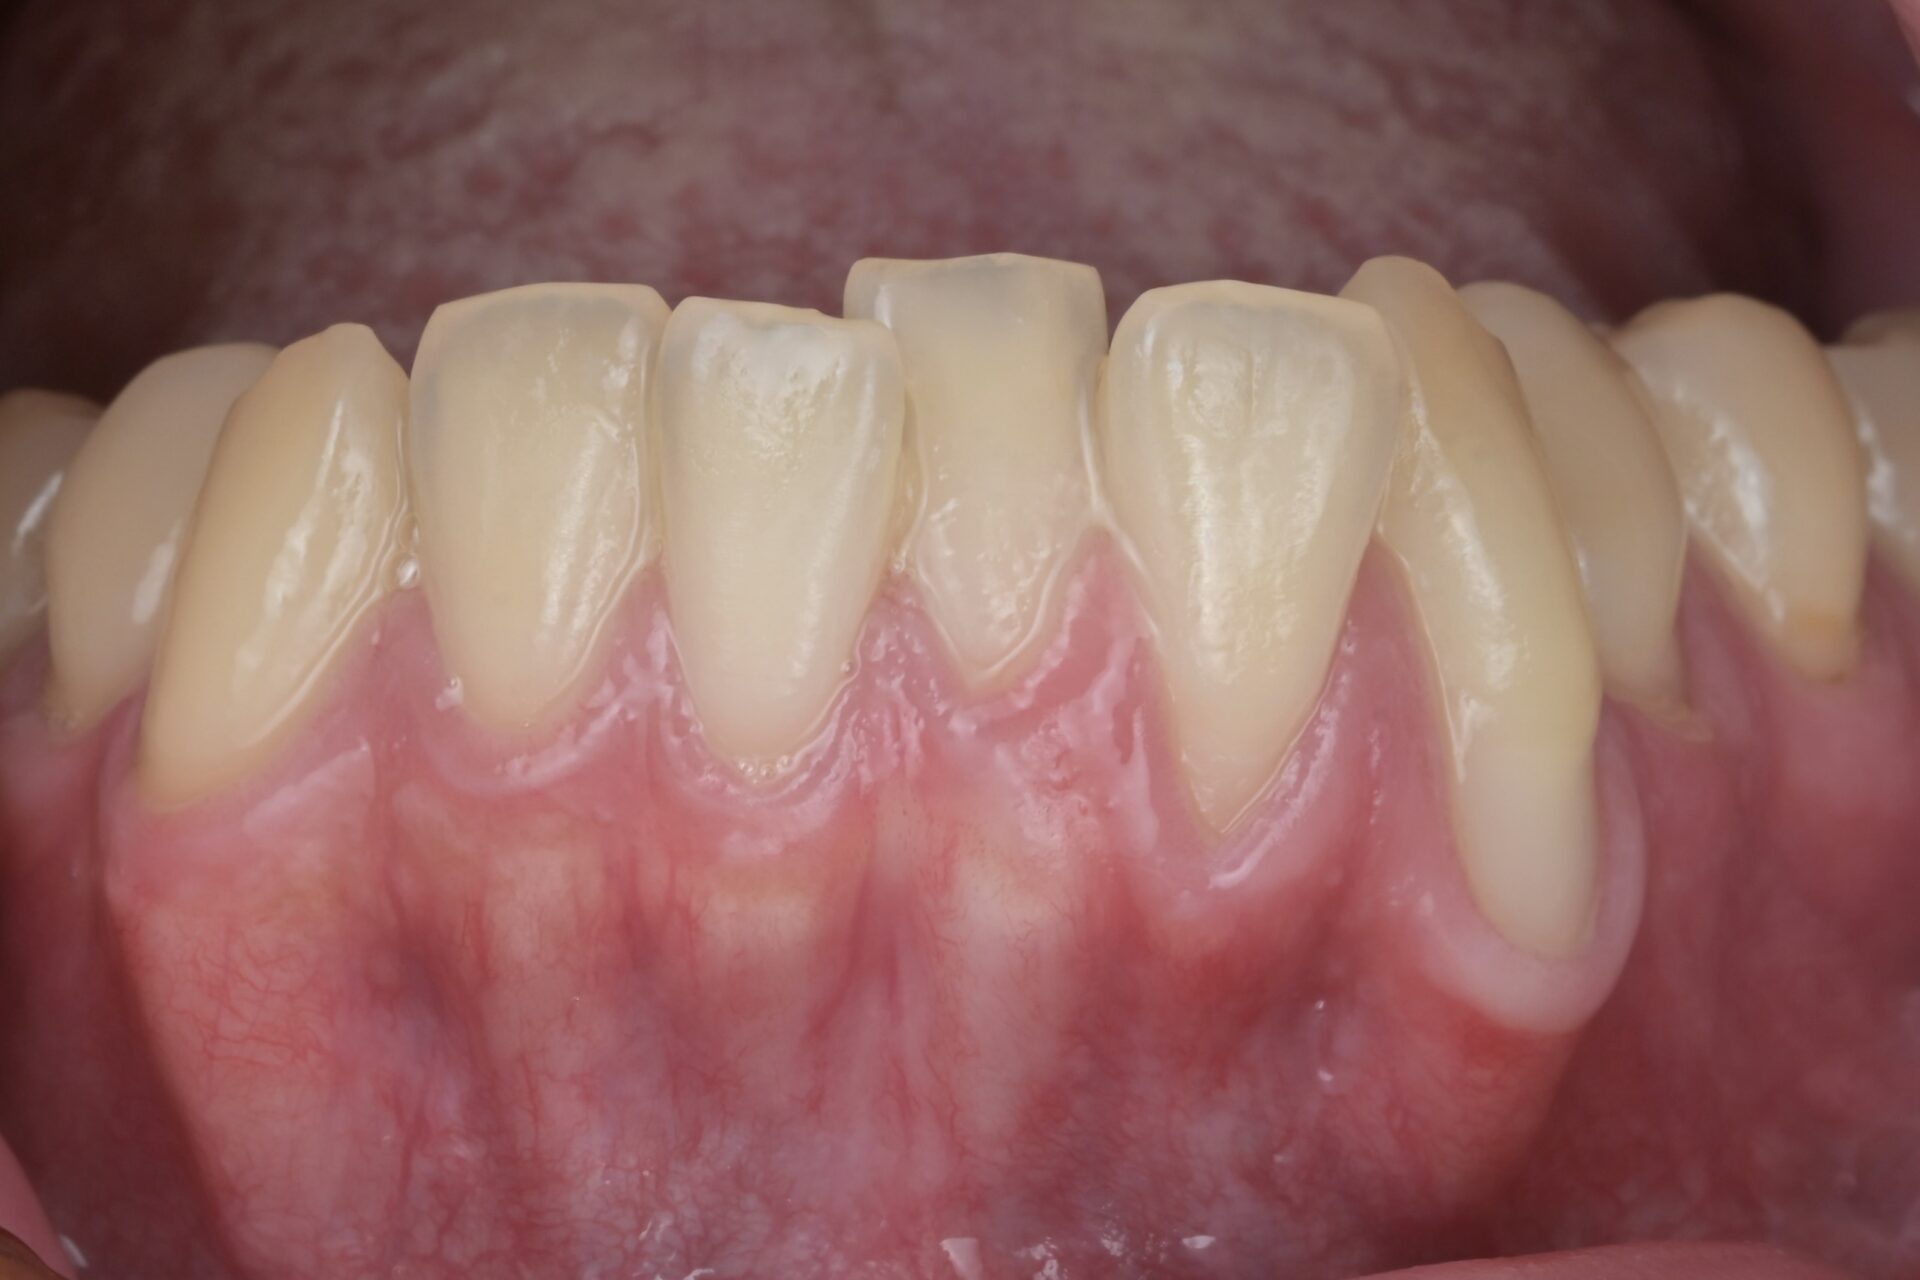

術前

歯垢を染め出してジェットパウダーでクリーニングします。麻酔が効いたら露出した根面を滑沢に硎磨します。 -